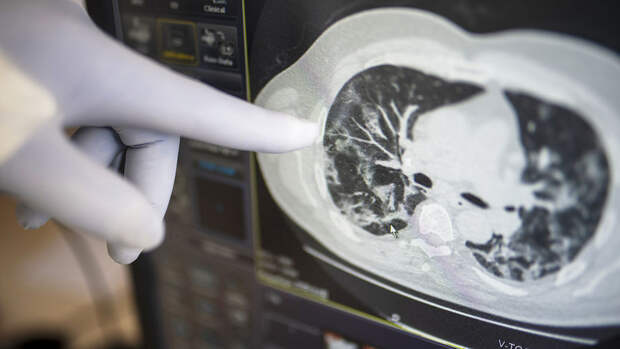

Ученые провели эксперимент на мышах: одну группу заразили коронавирусом, вторую - коронавирусом и гриппом. У второй группы заболевание протекало тяжелее.

"Даже при условии, что зараженным гриппом мышам вводился коронавирус с уменьшенной репликацией, у них наблюдалась усиленная воспалительная реакция. Это основная причина тяжелой формы COVID-19 у людей", - приводятся слова одного из авторов исследования Джеймса Стюарта.

Он подчеркнул, что смертность мышей, зараженных и коронавирусом, и гриппом, в шесть раз превысила показатели инфицированных только COVID-19 животных.